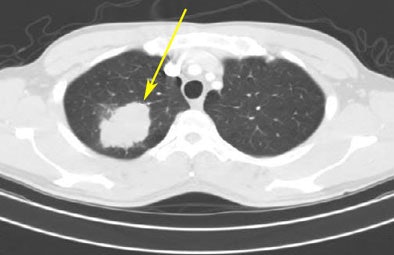

![]() |

| From the RIDER database, a lung cancer case is shown pretreatment (top) and post-treatment (bottom). |